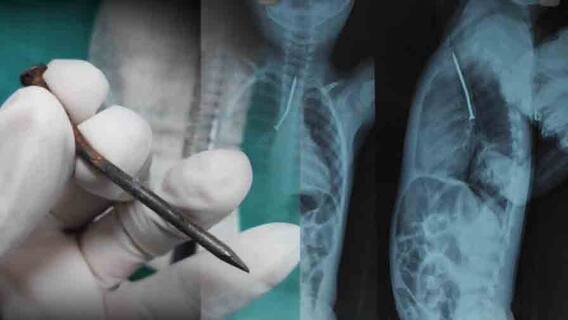

সন্দীপ সরকার, কলকাতা: এসএসকেএমে জটিল অস্ত্রোপচারে বাঁচল শিশুর প্রাণ। খেলতে গিয়ে আড়াই ইঞ্চির পেরেক গিলে ফেলে শিশু। শিশুর শ্বাসনালীতে আটকে যায় আড়াই ইঞ্চির পেরেক। দুই সরকারি হাসপাতাল ঘুরে রায়গঞ্জ থেকে এসএসকেএমে পরিবার। এক ঘণ্টার জটিল অস্ত্রোপচারে প্রাণ বাঁচল শিশুর। বের করা হল পেরেক।

বয়স মাত্র আড়াই। হাতের সামনে যা মেলে তাই নিয়ে খেলা। আর খেলতে খেলতে নিজের অজান্তেই বিপদ ডেকে এনেছিল উত্তর দিনাজপুরের রায়গঞ্জের ইটাহারের এই একরত্তি। বছর আড়াইয়ের শিশুর শ্বাসনালীতে আড়াই ইঞ্চির পেরেক। দুই সরকারি হাসপাতাল ঘুরে এসএসকেএমের চিকিৎসকদের তৎপরতায় বাঁচল প্রাণ।

কীভাবে পেরেকটা ঢুকল? হাতে পেরেক নিয়ে কী করছিল ওই শিশু? শিশুর পরিবার সূত্রে খবর,  শনিবার সকালে বাড়ির সামনে বেড়া দেওয়ার কাজ চলছিল। সেসময় খেলতে খেলতে পেরেক গিলে ফেলে একরত্তি। মুখ দিয়ে রক্তপাত শুরু হয়। শিশুর পরিবার সূত্রে খবর, প্রথমে রায়গঞ্জ হাসপাতালে নিয়ে যাওয়া হয় তাকে। এক্সরেতে দেখা যায় শ্বাসনালীতে আটকে রয়েছে পেরেক। রায়গঞ্জ হাসপাতালে চিকিৎসা পরিকাঠামো না থাকায় বিকেল ৪টে নাগাদ রেফার করা হয় মালদা মেডিক্যাল কলেজে।

সেখানেও অস্ত্রোপচারে পরিকাঠামো না থাকায় রেফার করা হয় এসএসকেএমে। রবিবার ভোরে অ্যাম্বুলেন্সে করে এসএসকেএমে পৌঁছয় শিশুর পরিবার। সকাল সাড়ে ৮টায় শুরু হয় অস্ত্রোপচার।বঙ্কোসকপি পদ্ধতিতে প্রায় ১ ঘণ্টা ধরে চলে অস্ত্রোপচারের পর বের করে আনা হয় আড়াই ইঞ্চির পেরেক। বিপদমুক্ত হলেও আপাতত শিশুটিকে আইসিইউতে রাখা হয়েছে।